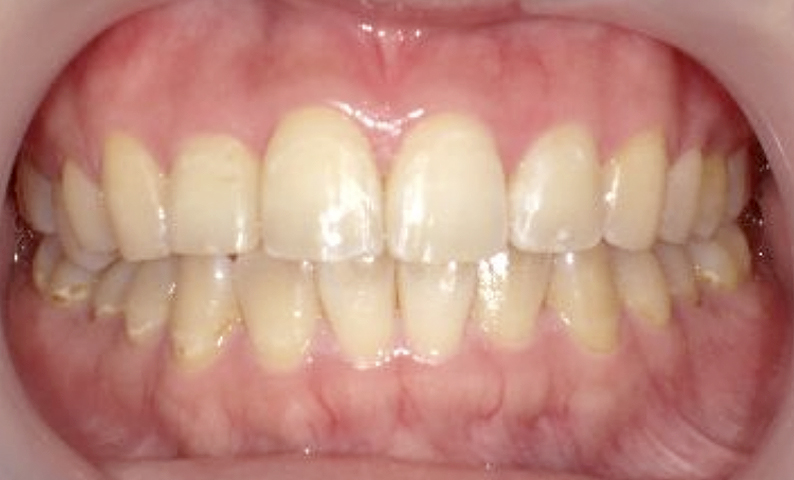

症例_023 上下顎の部分矯正

治療期間:11ヶ月金額:45万円+税女性前歯のガタガタ八重歯

| Before | After |

|---|---|

|